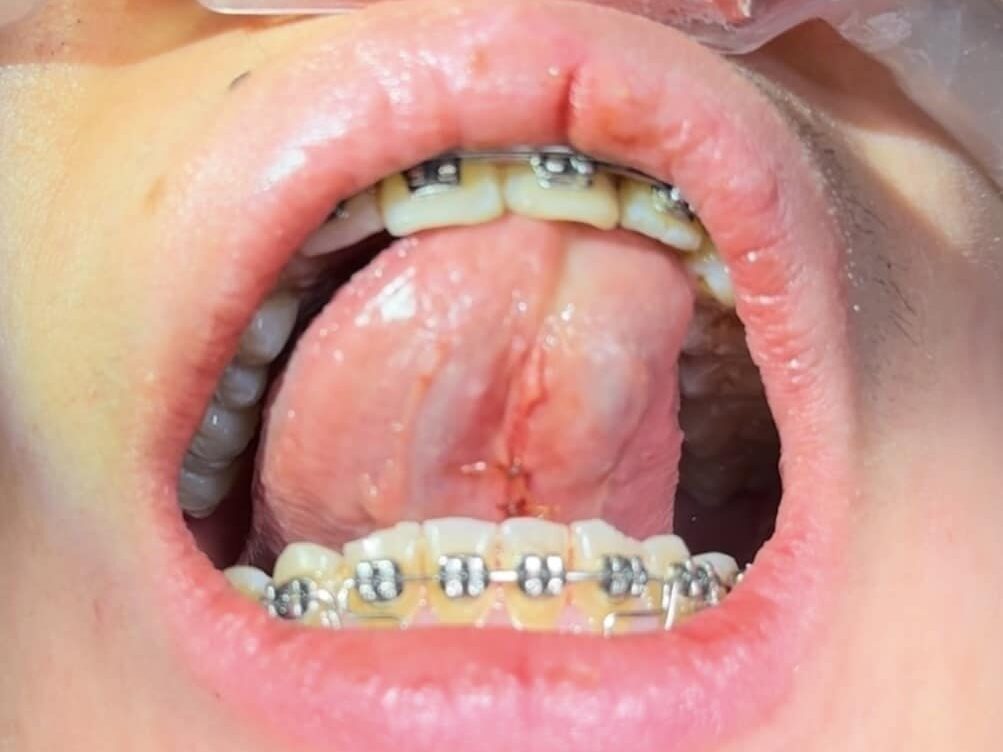

1 week post surgery sutures pic